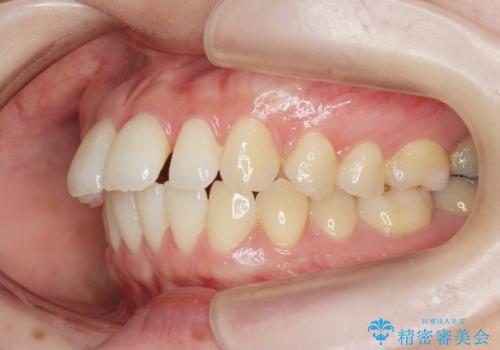

- 出っ歯に見える前歯を治したい、と矯正治療を希望され来院されました。

奥歯の噛み合わせに大きな問題はないので、目立つ前歯の角度・隙間を重点的に整え、審美的な歯並びを獲得できるよう計画します。

治療によりしっかりと前歯の角度が改善され、審美的な歯並びを手に入れることができました。